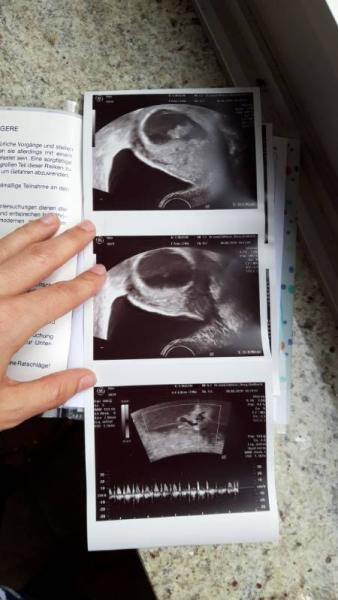

Hallo ihr lieben ich komme gerade vom Frauenarzt. Und hatte nun bei 8+6 meine zweite Untersuchung. Das Kind ist nun 2cm groß und hat eine kräftigen Herzschlag. Alles zeitgerecht entwickelt, und ich Mega glücklich.

Bild zu Gerate 2te Untersuchung hinter mir - Forum für Januar - Mamis

Ja das obere ist das Baby 2cm. In der Mitte die Fruchtblase 5cm Und unten die herztätigkeit. Mein Frauenarzt macht immer 2-3 bilder